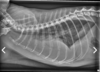

Radiographie d'un patient félin asthmatique (présenté en crise d'asthme) vs normal

The radiographic findings in this case are a diffuse bronchial pattern consisting of airway thickening appearing as so called "tracks and doughnuts." Terbutaline is a beta-2 agonist that allows bronchial smooth muscle relaxation and along with oxygen, are two important aspects of the emergency management of a cat in acute respiratory distress from asthma. In reality, you probably should have administered these therapies prior to radiographs as the stress of handling a cat in acute respiratory distress can be dangerous. Along those lines, restraining this cat to pull blood is similarly contraindicated until she has been stabilized. Thoracocentesis for pleural effusion or pneumothorax are inappropriate, as this cat does not have either of those problems at this time. Some of the "doughnuts" have been circled in orange. The bronchial pattern is diffuse throughout the lungs.